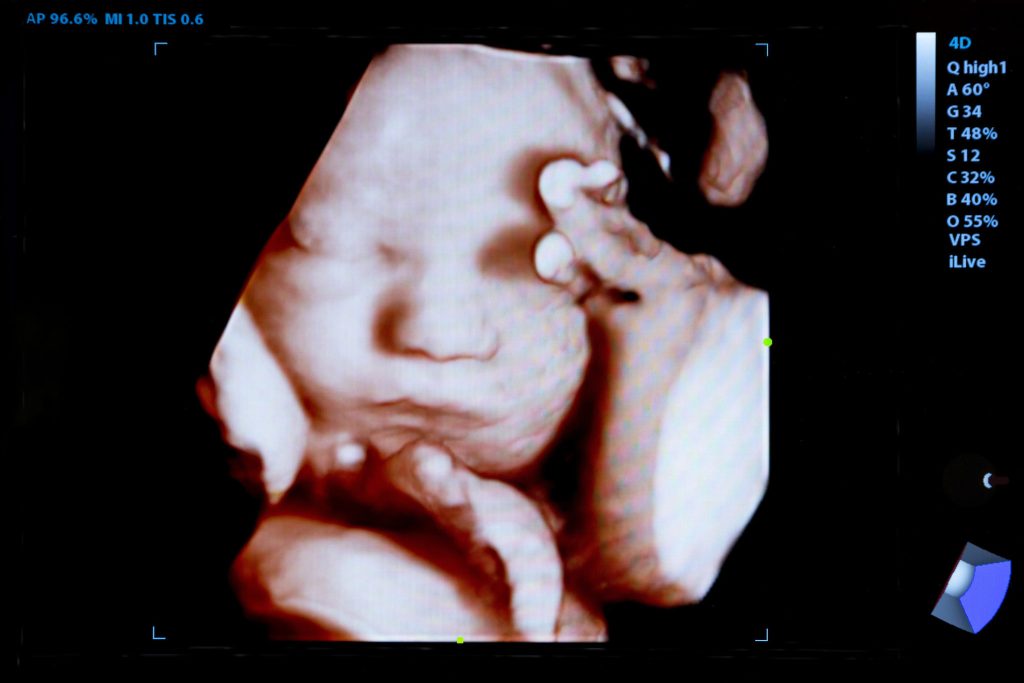

Late one night, Adreiona called a PreBorn! Pregnancy Clinic in a panic. “I took the abortion pill,” she said. “Everyone is telling me that since I am in college, I can’t manage a baby. Is it too late to save my baby?” she pleaded.

Sadly, the abortion industry sells a deceptive message that the abortion pill is an easy fix to a complicated situation. However, it is not that simple. Many girls take the abortion pill only to later regret their decision. Thankfully, there is a life-giving solution called the abortion pill reversal! If taken within 72 hours, the life of the baby can be saved.

Donors like you faithfully provide ultrasounds and counseling while helping to fund baby clothes, diapers, and formula. More importantly, your love gives a young mother an opportunity to hear the gospel of Jesus Christ. Check out the powerful impact our love makes.